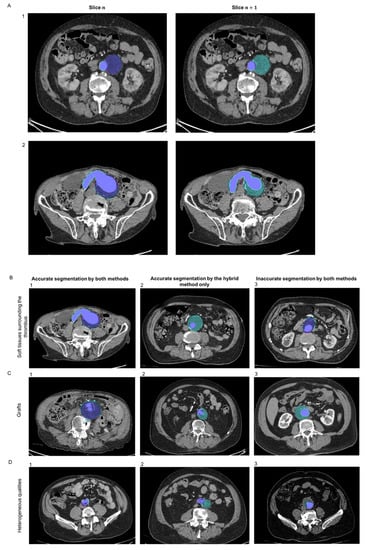

3.3. Lumen Segmentation

3.4. Thrombus Segmentation